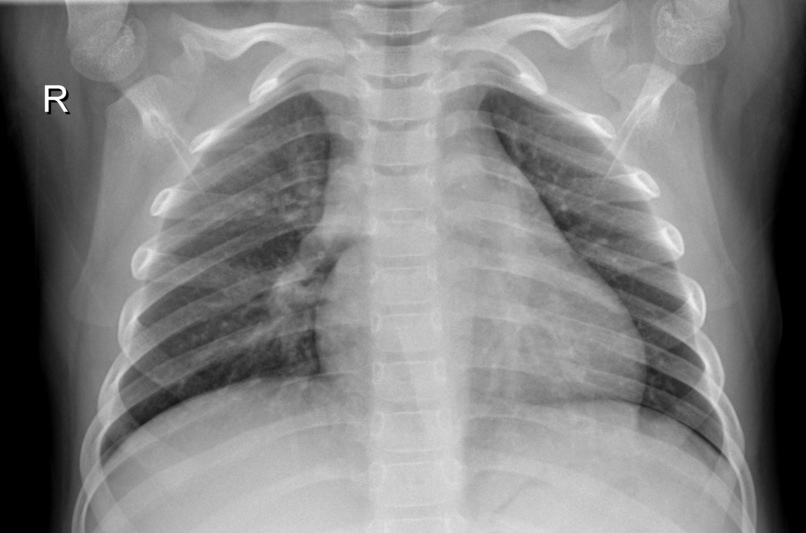

The AI Clinic webpage accepts medical images (such as xray, mri, photos) and outputs the diagnosis from those images. (Diagnosis include: Brain Cancer, Alzheimer's, Monkey Pox, Pneumonia). This is achieved through trained machine learning models. The webpage also automatically outputs the most cited Google Scholar research papers related to the specific diagnosis. And although, it is primarily intended for the use of medical professionals (doctors, nurses, technicians, etc) the general public can reap its benefits too.

Machine Learning Models: We have trained 4 machine learning models (for now!) - Brain Cancer, Alzheimer's, Monkey Pox, Pneumonia - from datasets obtained from reliable sources in Kaggle. To further increase accuracy, we also applied data augmentation to our datasets and used transfer learning techniques. Flask Framework: We created our webpage - frontend and backend - using the flask framework. JavaScripts and CSS added functionality and UI/UX components respectively. Microsoft Azure: We set up an Ubuntu Server on Microsoft Azure from scratch. We hosted our full-stack environment on the ubuntu server primarily to make it more production-friendly for us and for scalability in the future.